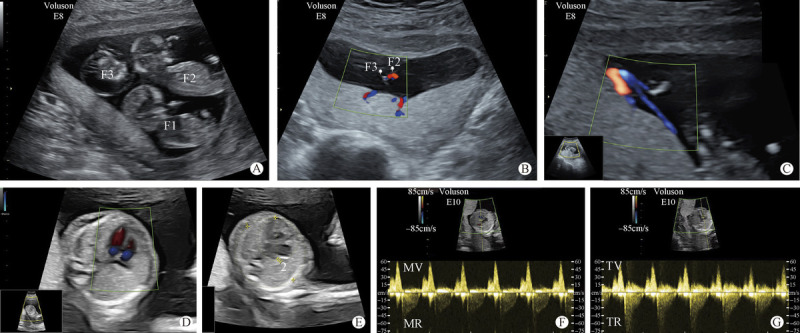

Intrauterine Treatment of Monochorionic Triamniotic Triplet Pregnancy with Twin Reverse Arterial Perfusion Sequence.